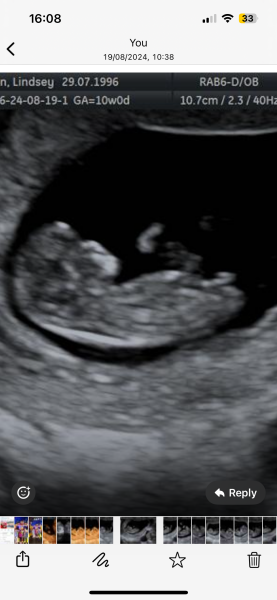

Hi guys I’ve been for my scan and I was 10 weeks and 4 days any idea on gender based off nub theory I have been told that during 10-12 weeks the nub can look relatively the same both boy and girl , but any ideas?

You can't do nub theory that early - even babies bang on 12 weeks tend to still look very girly. The nub doesn't start to rise until then, so they all look like early girls, but in 2 weeks time it could have risen into a boy nub.